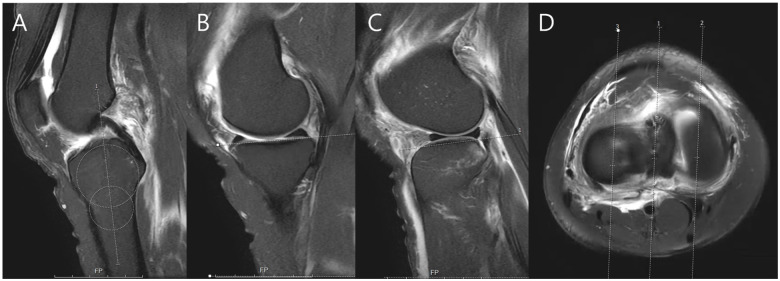

Purpose/hypothesis: The purpose of this article was to evaluate the accuracy of calculating the lateral plateau slope using lateral radiograph (LR) and magnetic resonance imaging (MRI)-derived asymmetry. It was hypothesized that measurement error would be high and variable across imaging modalities and that 3-dimensional (3D) reconstruction would serve as a consistent and accurate reference for PTS assessment.

Methods: Between March 2020 and October 2023, ACL reconstruction patients were screened. PTS was measured on knee LRs, tibial long-bone LRs (LLRs), preoperative MRI, and 3D-reconstructed images from postoperative computed tomography scans. Two orthopaedic surgeons performed 2 measurements each. Reliability was assessed using intraclass correlation coefficients (ICCs), and agreement was analyzed using Bland-Altman plots, considering ±2° limits of agreement (LOA) as acceptable.